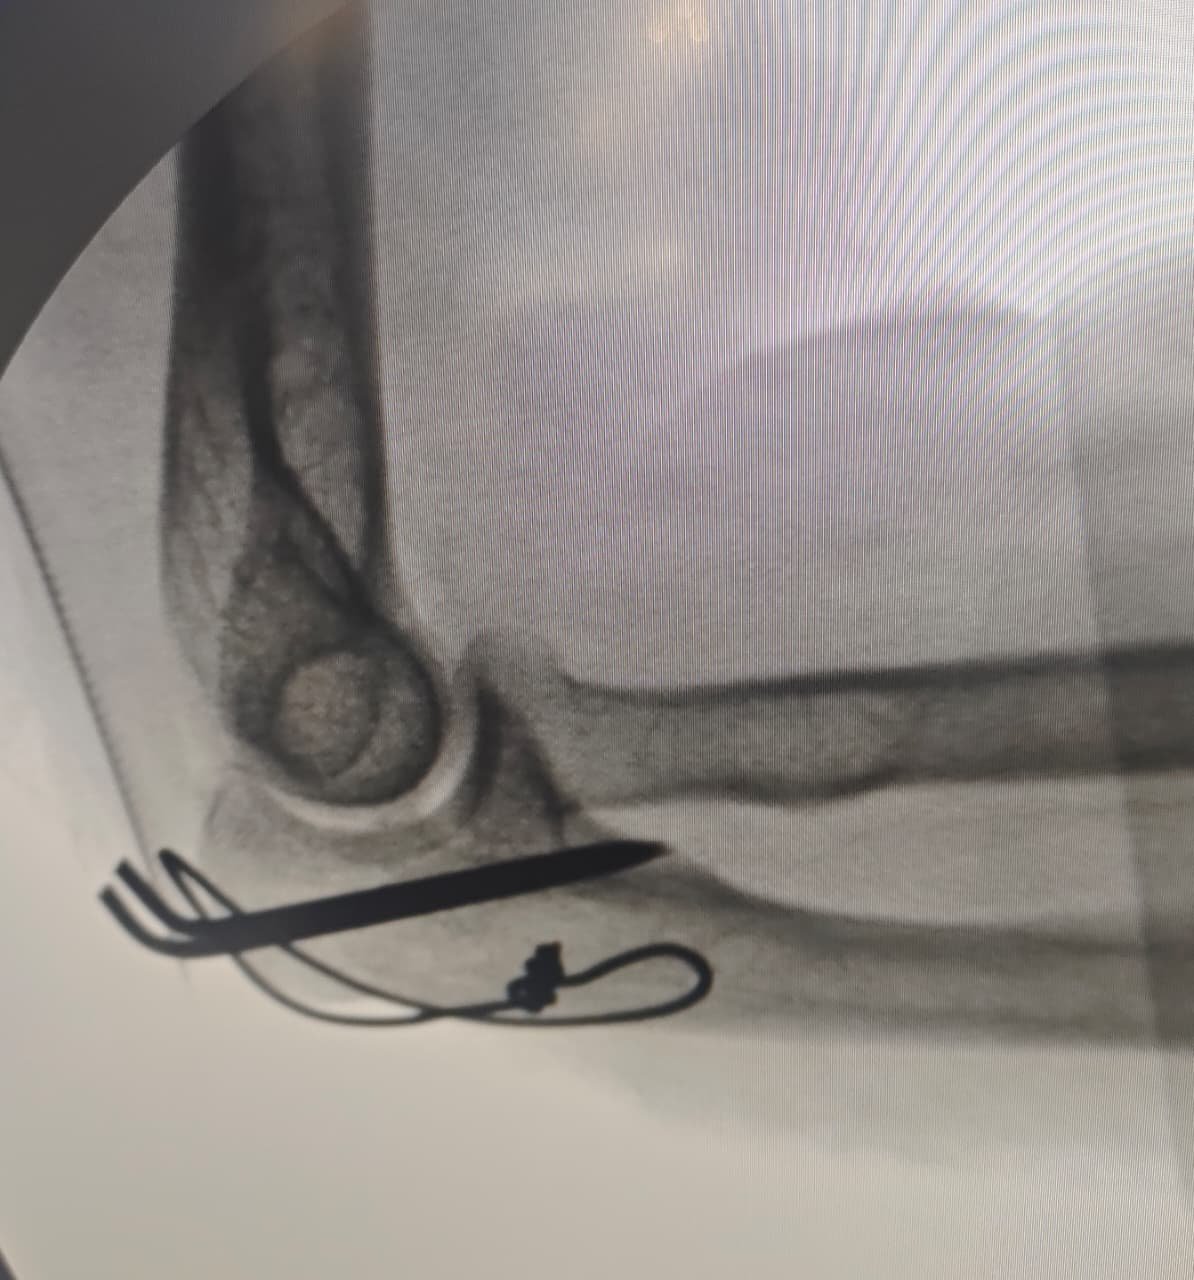

Fracture Care (Orthopedic Trauma):

◆ Expert management of orthopedic fractures, including complex traumatic and intra- articular fractures

◆ Surgical fracture fixation in absolutely indicated cases.